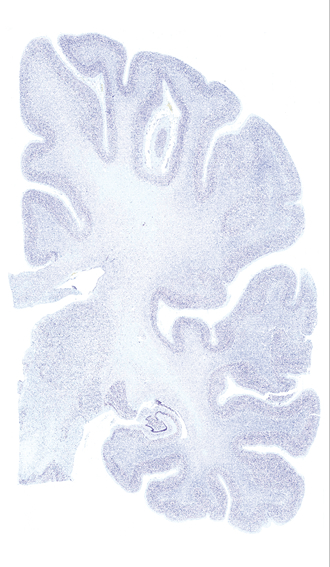

Hi-Resolution Sections · Cells (Nissl Staining) · Virtual Microscopy

Frontal sections (Nissl) from the Atlas Brain:

Slice ID:

r3-0349

Plate NR:

ca 43

Position:

28,0 mm